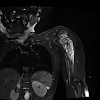

Radiology Flashcards: Peds was designed for radiology resident and pediatric imaging fellowship education. Physicians, residents, medical students, and anyone interested in pursuing a career in medical imaging will also find this app useful. Radiology Flashcards: Peds provides the user with 100 high quality interactive images including ultrasound, plain film, CT, and MRI. On the opposite side of the flashcard is the correct diagnosis followed by a brief fact that can be memorized.Keep track of the items you missed, optimize your study time, and focus on high-yield clinically relevant concepts.In collaboration with Hawki, Inc, makers of Radiology Flashcards for iOS.